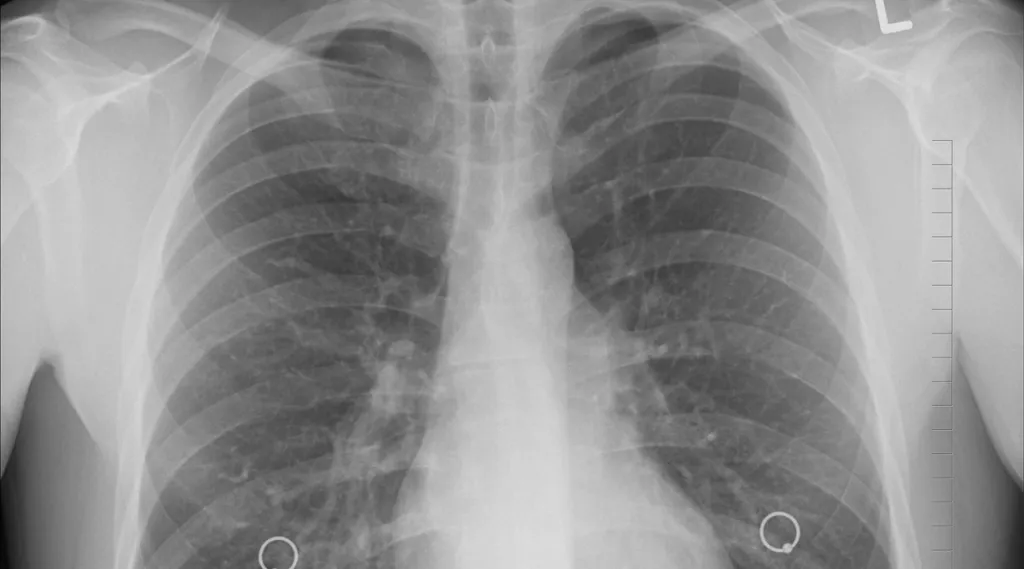

Research has indicated that microplastics can induce inflammation, oxidative stress, and impaired lung function. Humans are likely exposed to microplastics (mps) in a variety of places including indoor and outdoor air. Microplastics were identified in all regions of the human lungs using μftir analysis. (2021) detected microplastics in the lung tissue ranging from 1.60 to 16.80 μm. Jenner et al., 2022) and in the sputum. In rodent studies, microplastics have been shown to have detrimental effects on a wide variety of organs, including the intestine,. They identified 39 microplastics in 11 of the 13 lung tissue samples, with an average of 3. Researchers discovered microplastics in all the regions of the lung. Research has indicated that microplastics can induce inflammation, oxidative stress, and impaired lung function.